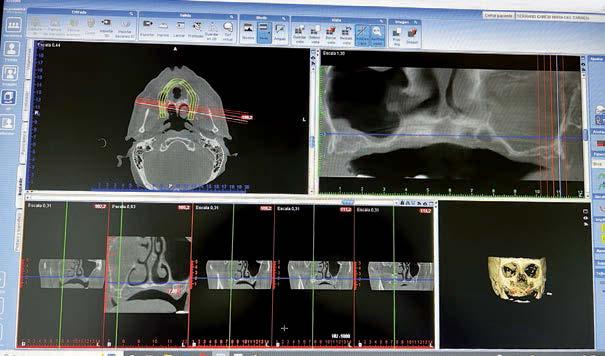

Fueron reclutados de forma retrospectiva pacientes en los que se hubiesen realizado ambas

técnicas de abordaje de seno maxilar: elevación convencional o la inserción de implantes cortos y extra-cortos mediante elevación transcrestal, desde enero de 2010 en adelante. Todos los pacientes fueron estudiados antes de la inserción de los implantes mediante modelos diagnósticos, exploración intraoral y realización de un TAC dental (Conebeam) analizado posteriormente mediante un software específico (BTI-Scan II).